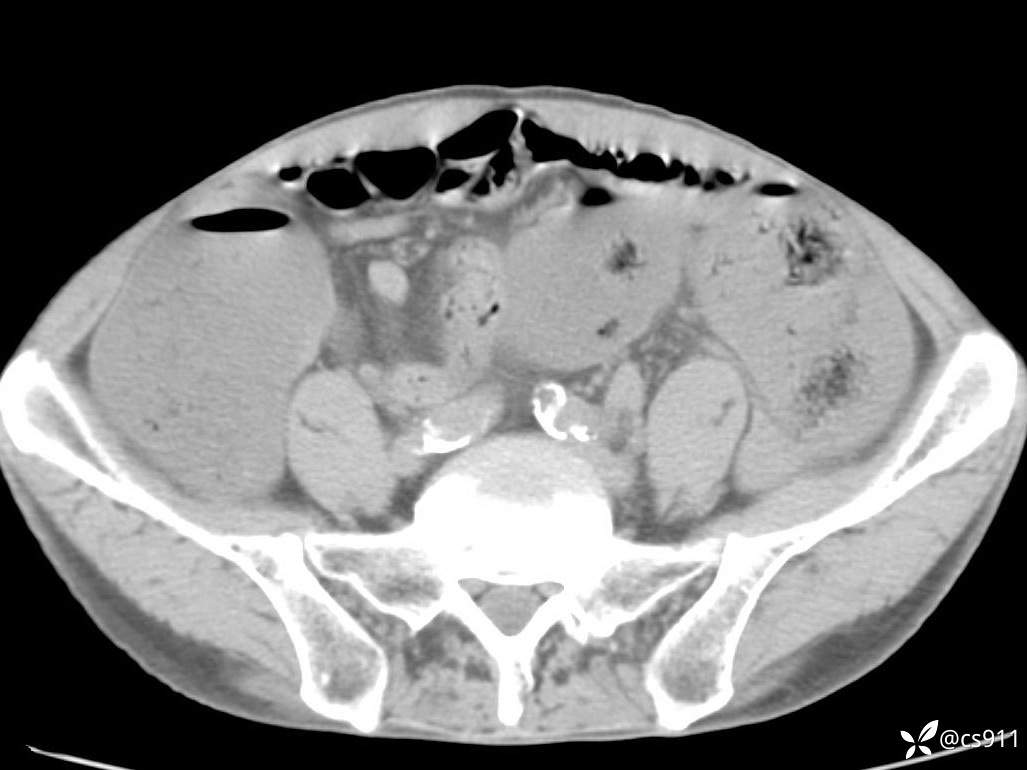

急腹症之急诊CT,原因?答案公布

男,77岁,腹痛、腹胀伴恶心呕吐1天。呕吐胃内容物,非喷射性呕吐,有咖啡色样胃内容物,诉有胃穿孔病史。查体:全腹平,下腹部压痛,全腹无反跳痛,叩诊呈浊音,移动性浊音阴性,肠鸣音减弱,1-2次/分。肛检:直肠未扪及明显肿物,可触及大量粪块。

血淀粉酶(AMY) HH 1859 U/L 35-135